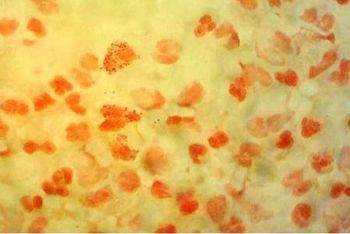

Initially treated empirically for acute bronchitis, this patient came to the ED with a 6-week history of worsening cough, dyspnea, fevers, weakness, and a 20-lb weight loss.